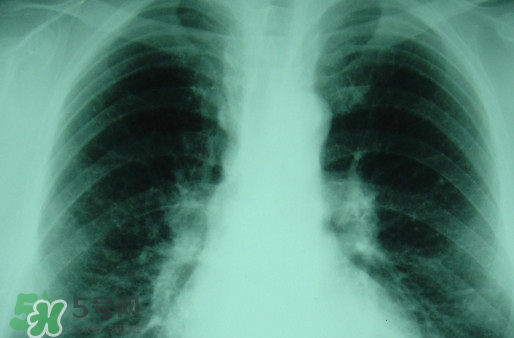

塵肺病多半是肺部灰塵太多導(dǎo)致肺部承載大清理工作降低導(dǎo)致的,對(duì)此有人提出換肺治療的方法。那么,塵肺病能換肺治愈嗎?塵肺病不能吃什么?